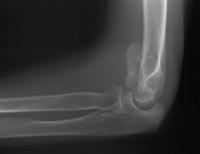

81 year old physically active woman sustained a left elbow fracture in a syncope related fall.

Lateral and central fracture component displacement.

Unusual contour visible at the medial metaphyseal flare.

This is seen on the lateral view to be the anterior half of the central articular surface.